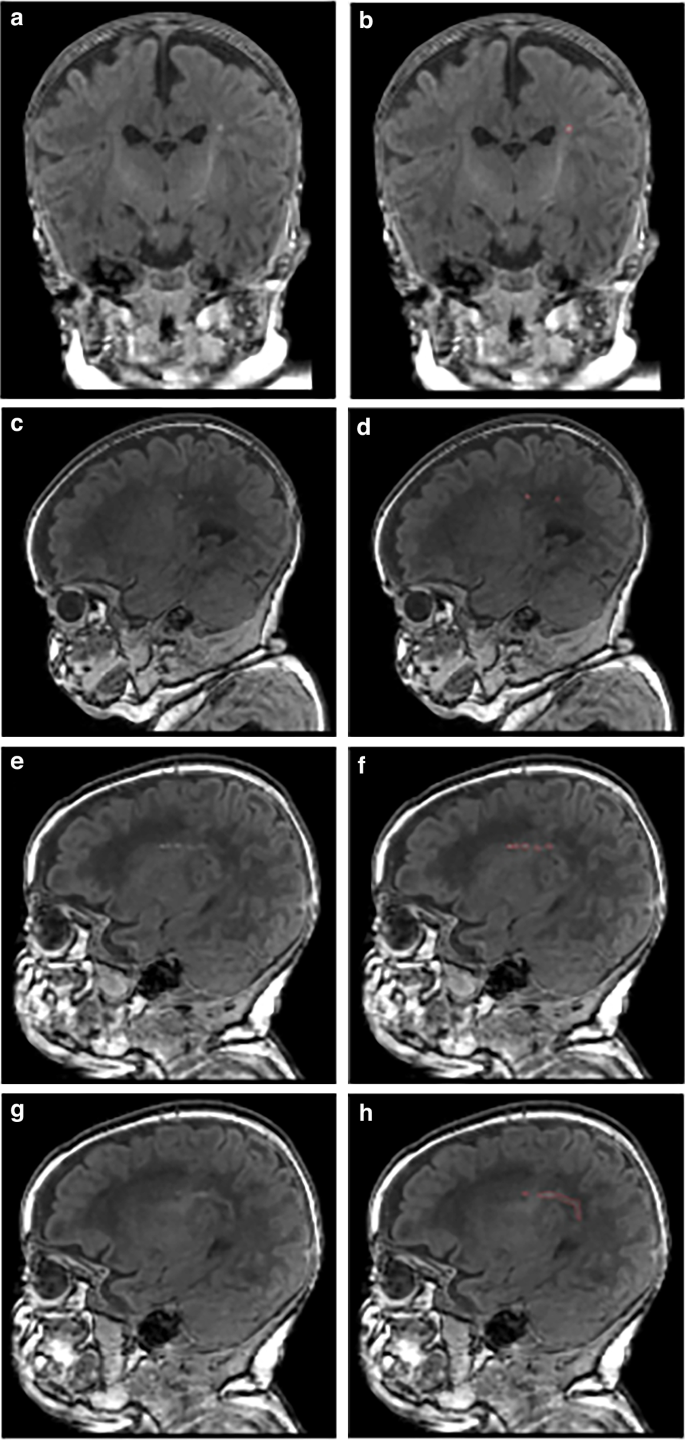

PWML was diagnosed qualitatively on anatomical MRI by a single experienced neuroradiologist as white matter non-hemorrhagic (SWI negative) T1 bright foci or white matter confluent non-hemorrhagic injuries (without T1 bright foci). T1-weighted images with qualitatively diagnosed PWML were manually segmented (Fig.1) as regions of interest (ROIs) by a trained rater as previously described.30 Briefly, using FSL (FMRIB), a single rater segmented voxels with bright signal intensity on T1-weighted images as PWML. All segmentations were reviewed for accuracy by an experienced neuroimaging researcher (NAP). Reliability testing was performed for both the radiologist (30 randomly selected MRI scans were reread four weeks later) and the trained rater (resegmented all PWML four weeks later while masked to prior results). MATLAB (R2019a) was used to calculate ROIs.

a 31 weeks’ gestational age (GA) infant with mild PWML (13 mm3; lowest tercile for volume [3–15 mm3]) in the left periventricular white matter. This infant also had another solitary lesion in the contralateral hemisphere (not shown); b corresponding segmented image; c 32 weeks’ GA infant with moderate PWML severity (71 mm3; middle tercile [23–71 mm3]) in the right central white matter. This infant also had a second contiguous sagittal slice with similar lesions and additional lesions in the contralateral hemisphere (not shown); d corresponding segmented image; e 28 weeks’ GA infant with severe PWML severity (185 mm3; highest tercile [75–338 mm3]) in the right central white matter; f corresponding segmented image; g same 28 weeks’ GA infant with more lesions in a contiguous sagittal slice; this infant also has a third contiguous slice with lesions and additional lesions in the contralateral hemisphere (not shown); h corresponding segmented image.

We categorized PWML volume (referred to as PWML severity) by thresholding it into terciles. This resulted in categorizing 364 infants with no PWML, 9 with mild, 10 with moderate, and 9 with severe lesions (ordinal; Fig. 1). The categorization of PWML volume was necessary for the antecedent analysis because this data was heavily skewed (93% of subjects had a volume of 0) and there was no data transformation that would allow use to use linear regression analysis without violating the main assumptions of this approach. The choice of terciles over dichotomizing PWML volume data allowed us to preserve more statistical power to identify antecedents. In bivariable analyses controlling for PMA at MRI scan, several antecedent factors were associated with PWML severity at p < 0.15, including ANS (p = 0.031), maternal smoking during pregnancy (p = 0.145), maternal use of opioids/narcotics during pregnancy (p = 0.008), moderate-severe HCA (p = 0.072), days on mechanical ventilation (p = 0.117), length of parenteral nutrition (p = 0.046), and caffeine therapy (p = 0.051). Notable non-significant factors included birth weight (p = 0.272), GA (p = 0.305); sex (p = 0.962), 5-minute Apgar score (p = 0.757), and intubation at birth (p = 0.578).